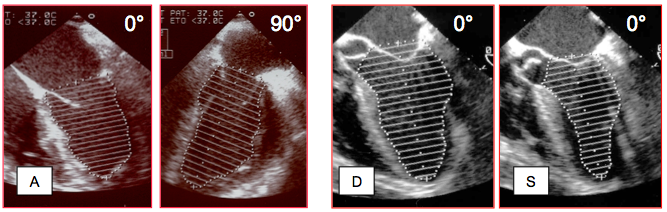

Le premier pas de l’évaluation fonctionnelle est un examen global du cœur en 4-cavités (vue mi-œsophage 0-20°), car celle-ci fournit le cadre général dans lequel vont s’inscrire les différents indices mesurés. Il permet de relever la taille respective des chambres cardiaques, leurs relations, leur dilatation et leur éventuelle hypertrophie. Cette vue générale est capitale pour intégrer les calculs détaillés qui n'expriment qu'une vue partielle de la réalité. Tout résultat ultérieur doit être compatible avec la silhouette fonctionnelle des cavités et des gros vaisseaux. L'image 4-cavités permet aussi quelques observations intéressantes (Figure 25.170).

Figure 25.170 : Vues 4-cavités 0° pour l'évaluation visuelle de la fonction du VG. A: cœur normal; la paroi du VG est musclée, la taille du VG et de l'OG est normale, la zone apicale apparaît pointue, la fraction d'éjection est 0.7. B: insuffisance chronique du VG; le ventricule est dilaté, sa paroi amincie, la zone apicale est arrondie, le débattement du feuillet antérieur de la mitrale est faible (flèche verte). C: lorsque la fonction du VG est normale, le débattement du feuillet mitral antérieur est ample; le feuillet est presque parallèle au septum en diastole. D: insuffisance mitrale restrictive sur dysfonction et dilatation du VG; les feuillets sont retenus en-dessous du plan de l'anneau mitral en systole (trait pointillé blanc) et la valve fuit.